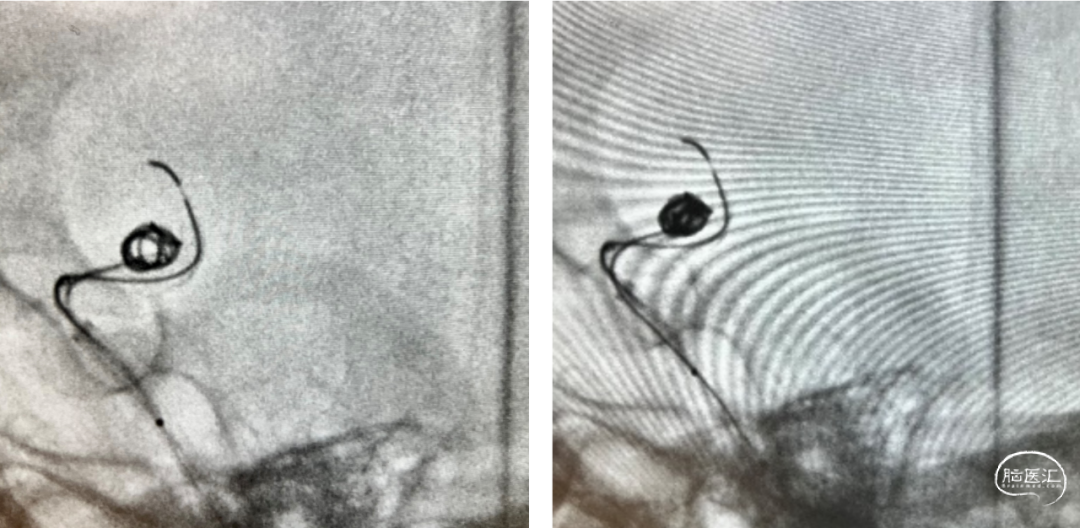

造影显示动脉瘤达到完全致密栓塞,撤出栓塞微导管。

继续缓慢释放Nuva®支架,在血管过弯处及支架尾端释放时注意随时调整系统张力,确保支架完全打开。

【过弯及尾部支架打开良好】

完全释放支架后,工作位造影可见支架显影清晰,形态良好,无贴壁不良,遂采取固定输送导丝,向前推送微导管,待微导管穿过装置后,将输送导丝远端回撤入微导管内,撤出支架输送系统。

为保证Nuva®血流导向密网支架的充分贴壁,支架完全释放后,微导丝弓背进入,进行支架内充分“按摩”,使之充分贴壁。

术后工作位及多角度观察,可见Nuva®血流导向密网支架打开良好、充分贴壁,颈内动脉血流正常,动脉瘤腔内可见明显造影剂滞留,分支血管保留良好,手术顺利结束。

【术后右侧颈内动脉正位造影】 【术后右侧颈内动脉侧位造影】

【术后右侧颈内动脉正位造影】 【术后右侧颈内动脉侧位造影】